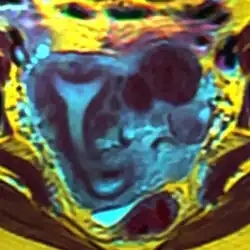

The arcuate uterus is a form of a uterine anomaly or variation where the uterine cavity displays a concave contour towards the fundus. Normally the uterine cavity is straight or convex towards the fundus on anterior-posterior imaging, but in the arcuate uterus the myometrium of the fundus dips into the cavity and may form a small septation. The distinction between an arcuate uterus and a septate uterus is not standardized.